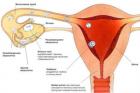

Овуляция. Определение овуляции (Видео)

Зачатие и развитие плода (Видео)

Определение беременности (Видео)

Как понять, что наступила беременность?